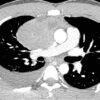

1. U quái lành tính

– Kích thước lớn 3-25cm. Tỷ trọng hỗn hợp, gồm các thành phần:

+ Thành phần nang (90%): 1 hoặc nhiều ổ, thành dày 1-5mm lát bởi tế bào biểu mô tiết chầy nhầy, có thể có vách, sau tiêm ngấm thuốc viền và vách. Các nang lông, tuyến da, cơ và thành phần mô mềm nằm trong nang.

+ Thành phần chất béo (76%): có thể tạo mức dịch-mỡ (10%)

+ Thành phần mô mềm: đồng nhất, ngấm thuốc sau tiêm.

+ Vôi hóa (53%): thường hình vành khăn, có thể thấy vôi hóa hình răng và xương (26%).

– U quái chưa trưởng thành thường chỉ có thành phần đặc.

– Khi có biến chứng vỡ tỷ trọng các thành phần không đồng nhất.2. U tế bào mầm ác tính

– Thành phần đặc chiếm ưu thế, mỡ (40%).

– Hoại tử, chảy máu, ít vôi hóa.

– Ngấm thuốc không đều sau tiêm.

– Biểu hiện di căn: xâm lấn thành ngực, màng phổi, màng tim, hạch vùng, di căn xa.V. Phân biệt